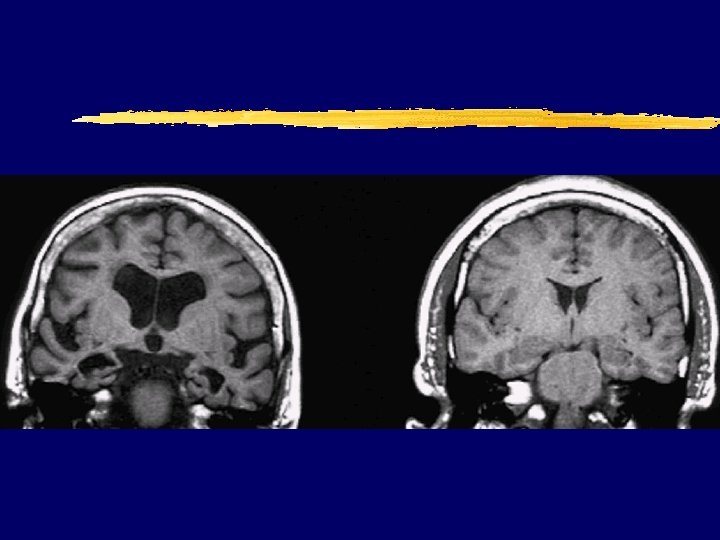

AD (70 y. ) vs normal brain (70 y. ) MRI